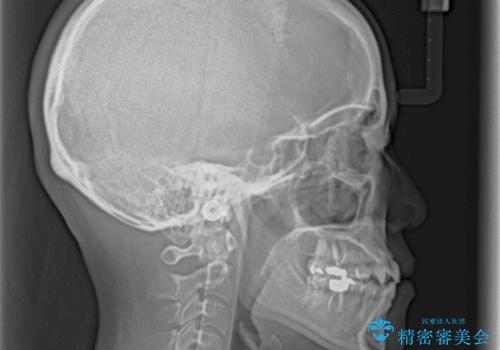

上顎骨の横幅が狭く、歯列が混み合っていたため、急速拡大装置により側方拡大し、咬み合わせと歯列を改善することとしました。

骨格的な問題を解決したことで、下顎は部分矯正で対応することができました。